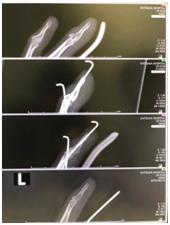

手术后,根据医生的要求,小杜服用了三天的止痛药、抗生素、消炎药。然后,一周复诊一次,确认骨头有没有歪,有没有其他异常等。医生每次都很仔细看片子,告诉小杜骨折部位的恢复情况等。这让小杜感到十分安心。

过了四周,小杜回到医院拔掉了两条钢针。听说拔钢针时一般都要打局麻,可是这位医生技术非常好,不打局麻也直接拔掉了,而且拔完小杜没有感受到一丁点的疼痛,直呼太神奇了。